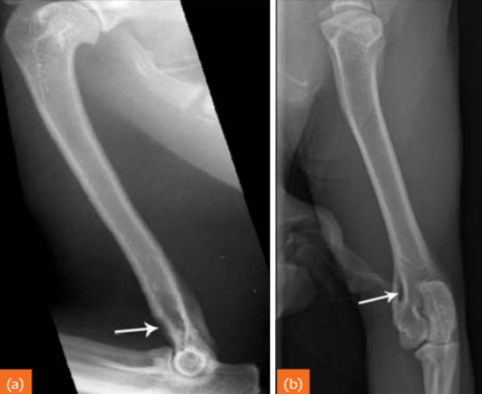

Describe Premature closure of growth plate.

e.g. distal ulna such as in image

results in growth discrepancy and may disrupt the function of the joint

What does this depict?

Premature closure of growth plate distal radius.